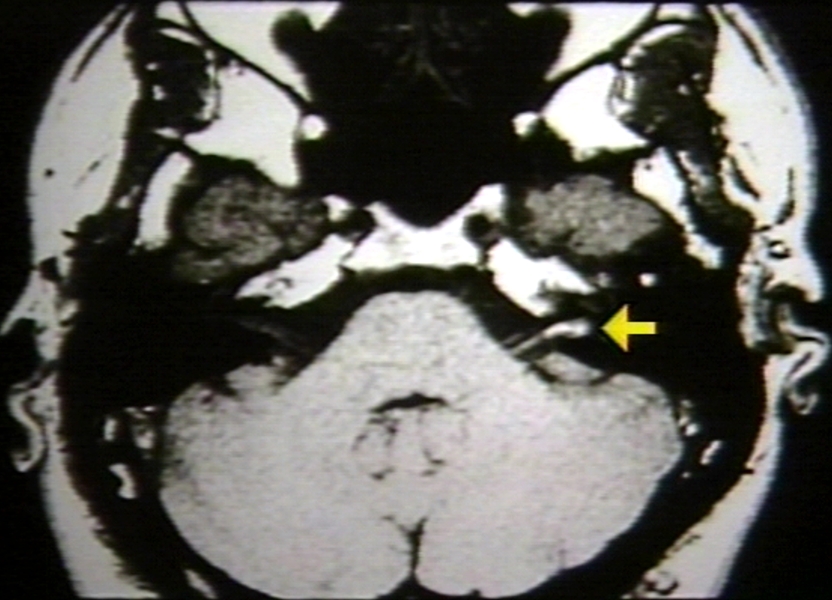

RADIOLOGY: EAR: HEMORRHAGE, INTERNAL AUDITORY CANAL; COULD BE HEMORRHAGIC ACOUSTIC NEUROMA OR NERVE SHEATH (MRI)